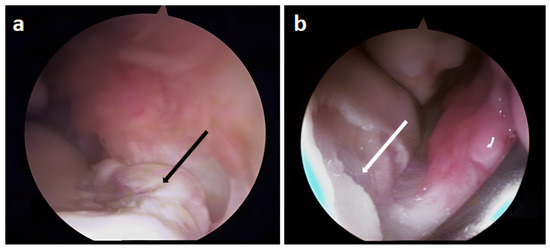

3.2. Arthroscopic Evaluation of the Lesion Site